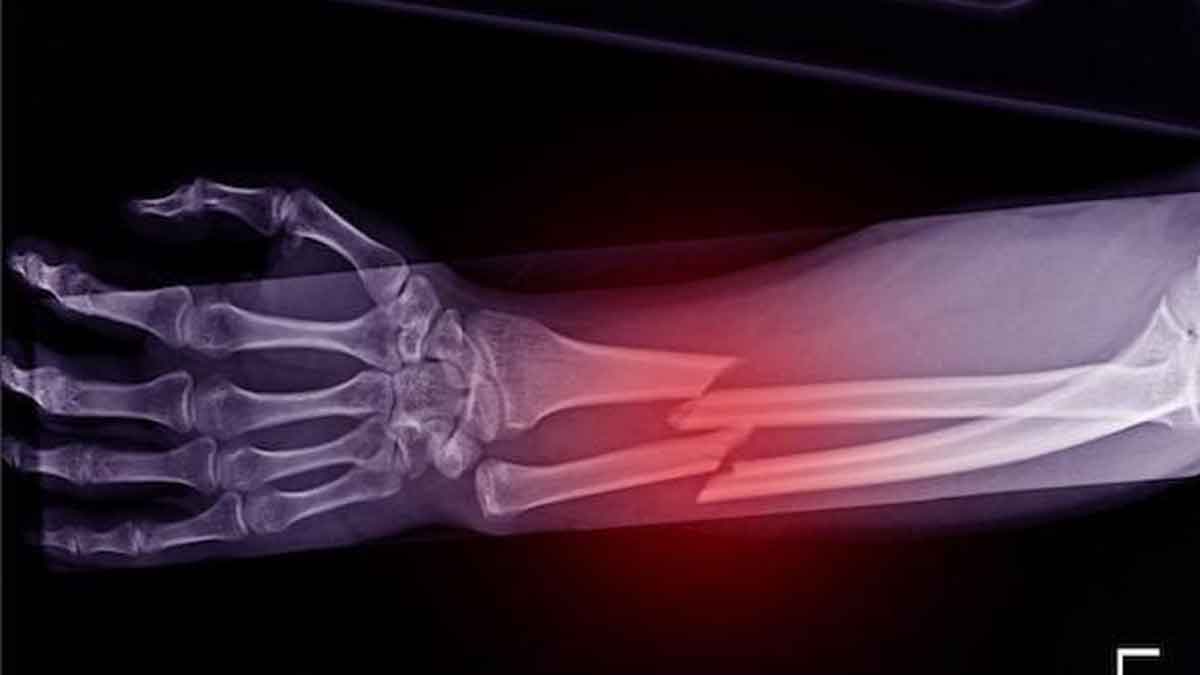

Bones Health : చలికాలంలో ఆహ్లాదకరమైన వాతావరణంతో పాటు అనేక రకాల అనారోగ్య సమస్యలు కూడా మనల్ని వెంటడతాయని చెప్పవచ్చు. చలికాలంలో మనల్ని వేధించే అనారోగ్య సమస్యలల్లో ఎముకలకు సంబంధించిన సమస్యలు కూడా ఒకటి. చలికాలంలో ఎముకలు బలహీనపడి విరిగే అవకాశాలు ఎక్కువగా ఉంటాయి. శీతాకాలంలో ఎముకలు విరగడం 20 శాతం ఎక్కువగా ఉంటుందని నిపుణులు చెబుతున్నారు. కనుక మనం శీతాకాలంలో ఎముకలు ధృడంగా ఉంచే ఆహారాలను ఎక్కువగా తీసుకోవాలి. ఎముకలను ధృడంగా చేసే ఆహారాల గురించి … Read more